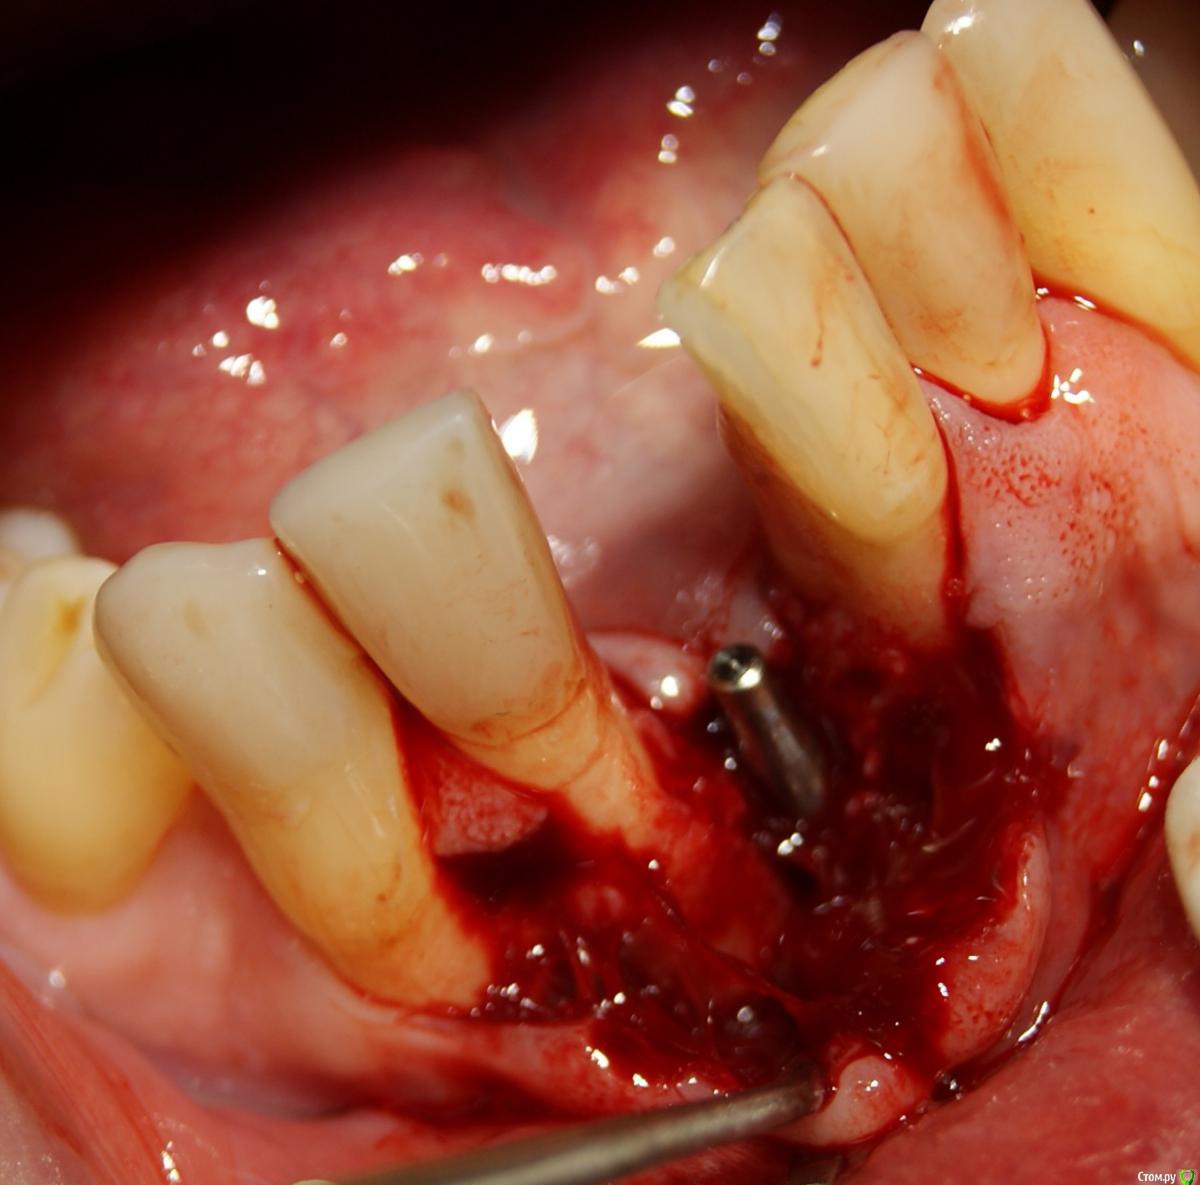

Jurai Опубликовано 25 декабря, 2016 Поделиться Опубликовано 25 декабря, 2016 *Предупреждение: фото на "мыльницу", не все этапы удались, но я работаю над этим) Вот пациент. Приятнейший, во всех отношениях, с негативным отношениям к мостовидным конструкциям. Полтора года лечил 41з по поводу периодонтита: толку не вышло. Удалил у широко известного многим стоматологам, особенно выпускам последних годов, доктора с ученой степенью. После удаления 4 месяца, по КТ область вполне достойно выглядит. Вот с чем пришел, обычное дело, все прилично: Раскрываю, а там между тонкими кортикалками мягко и упруго - резидуальная, фото нет. Открываю сильнее чем обычно, с расстройства не особо удачно. Кюретаж : Вид после, ушла вестибулярная кортикальная вместе с кистой: Сверлим 2,0, позиционердля рентген-контроля Имплантат ADIN UNP2,75Х11,5мм Ауто, джейсон коллагенфлис (что было под рукой) Швы. Контроль, перещелкивать не стали. В общем, понравился имплантат, для себя пометку кюретажить тщательнее, не надеяться, что организм все переварит. 1 9 Ссылка на комментарий